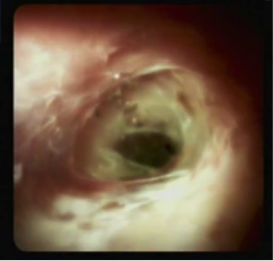

SpyGlass® Digital Cholangiopancreatoscopy

During ERCP, the bile duct is visualized using X-rays – contrast is injected into the bile duct which shows up on X-ray, and pathology is diagnosed by areas that don’t fill or are narrowed. Cholangiopancreatoscopy is a novel and exciting technology that allows a small camera to be inserted into the bile duct or pancreatic duct so that the inside of the duct can be examined visually. In addition, biopsies can be targeted to areas that look especially suspicious, increasing the chance of making an accurate diagnosis.